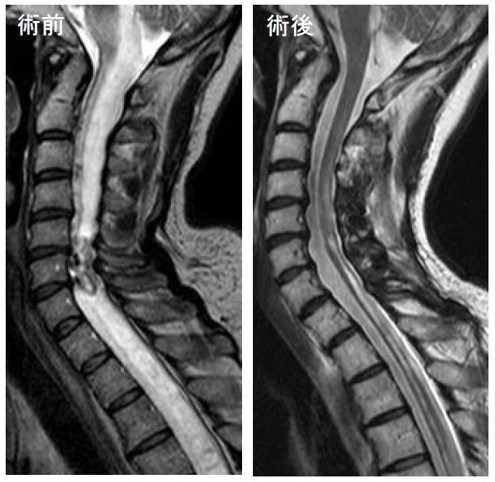

脊髄腫瘍(頚椎・髄内・血管芽細胞腫)

頚椎後方到達法による脊髄腫瘍摘出術(髄内)